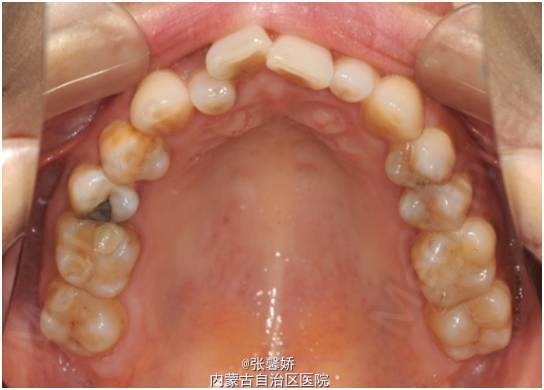

牙列中度拥挤;A2、D4反合 处理:时代天使隐形矫治器矫治 拔除C8、D8 适当下前牙邻面去釉 排齐整平上下牙列,改正A2、D4反合 治疗时间2年左右,矫治后牙齿排列整齐,咬合关系良好,患者满意。

一年后随访,患者咬合关系仍稳定,尖窝锁结良好。 隐形矫治适应证的选择很重要,适合中低难度的成人病例,患者的配合和依从性要求较高。 此患者术前全景片可见多个充填物,为龋易感患者,而且牙周也不是很好,隐形矫治没有拖槽更利于患者口腔卫生的维护,防止龋病的发生和牙周病的加重。